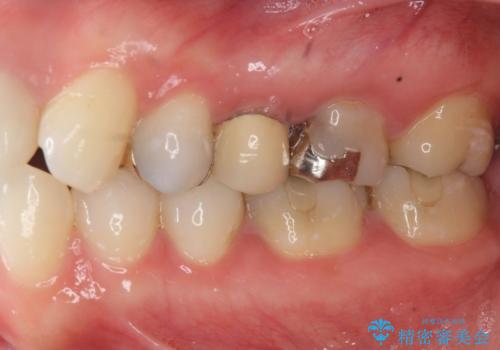

- 「笑った時に見えてしまう銀歯、古くなった修復物を白くきれいに治したい。」と希望され来院されました。

銀歯の下に再発していた虫歯を丁寧に取り除き、精密なセラミッククラウンで再治療を行います。

- 36.3万円(仮歯・ジルコニアクラウン×3)費用は治療当時の料金となります

噛み合わせが強く、銀歯やクラウンは大きくする減ってしまっている状況でした。

噛み合わせをしっかり調整することで、安定した咬合関係を得ることができました。